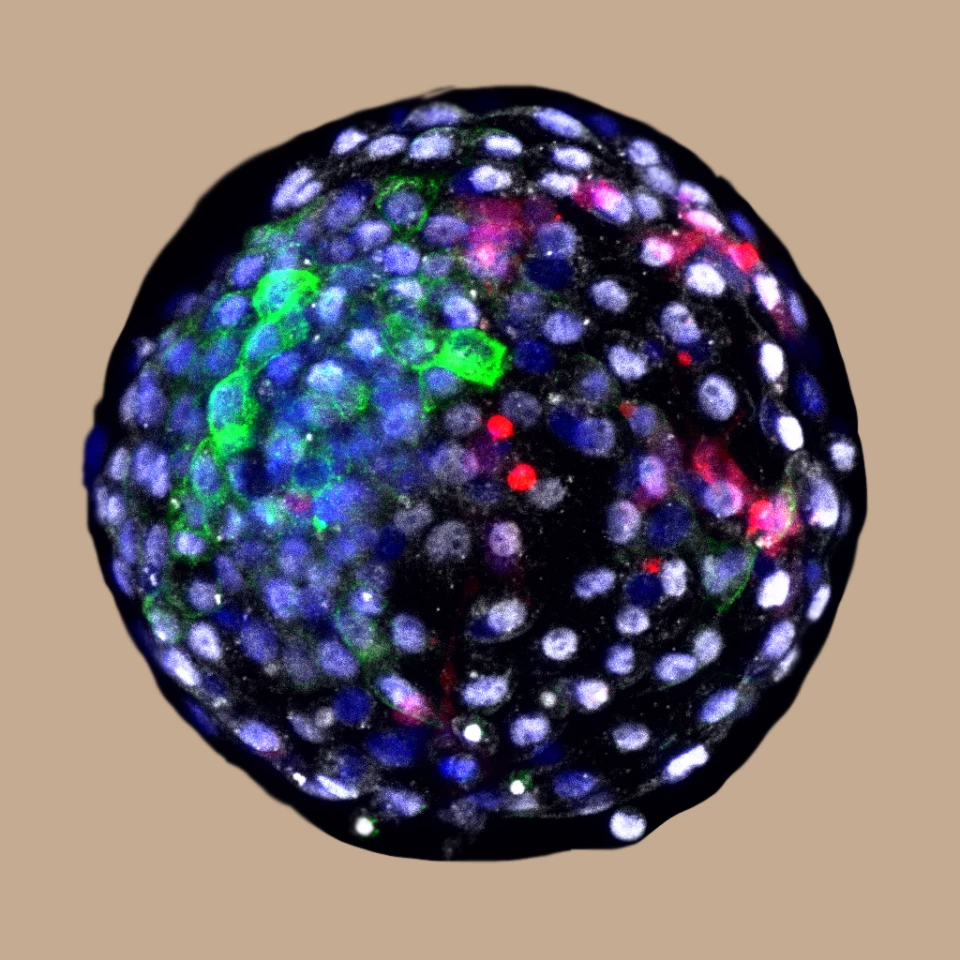

In lab tests in culture, the team started with monkey blastocysts. Six days after fertilization they were injected with 25 human extended pluripotent stem (hEPS) cells, which contribute to the tissue as the embryo develops.

And sure enough, when the researchers examined the batch of embryos 24 hours later, they detected human cells in 132 of them. After 10 days, there were 103 of these chimeric embryos remaining, but by day 19 only three still survived. After that, the embryos were terminated before they developed any further.

This successful experiment showed that human cells can survive and proliferate in monkey embryos, in relatively high numbers. The goal, the team says, is to make better models for studying biological development, evolution, disease progression and treatments.